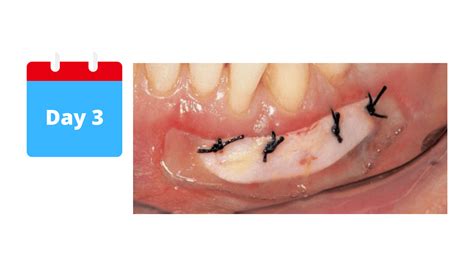

• Surgical Excision: This involves cutting off the skin tag using a scalpel or scissors. The procedure is typically performed under local anesthesia and is usually painless.